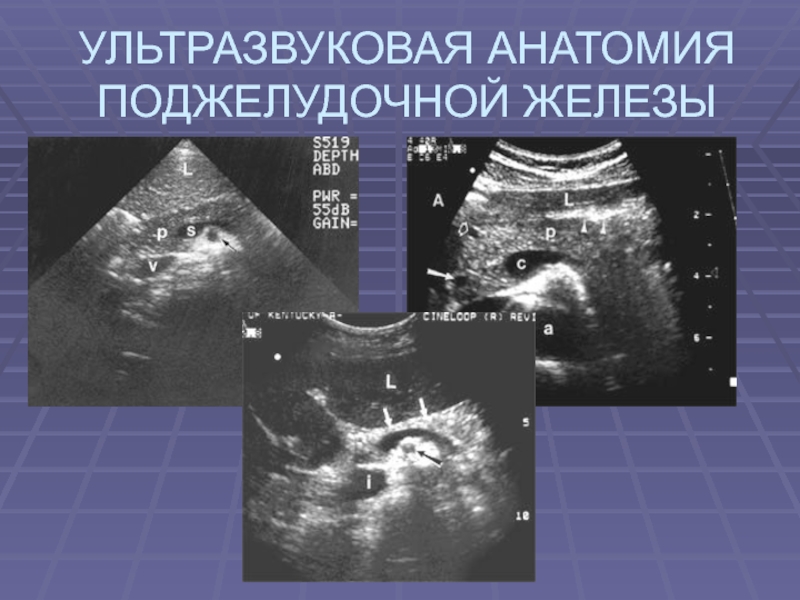

При УЗИ выявляется в эпигастральной области впереди

от магистральных сосудов: НПВ, аорты и позвоночного столба

Маркеры – сосуды НПВ, аорта, ВБА и

ВБВ, чревный ствол и его ветви, лежащие краниальнее, селезеночные сосуды,

проходящие по задне - нижней поверхности хвоста и гастродуоденальная артерия

НПВ в положении поперечного и косого сканирования

выявляется как жидкостная элипсовидная структура с коротким передне - задним

диаметром и выявляется сразу кзади от изображения головки железы - v;